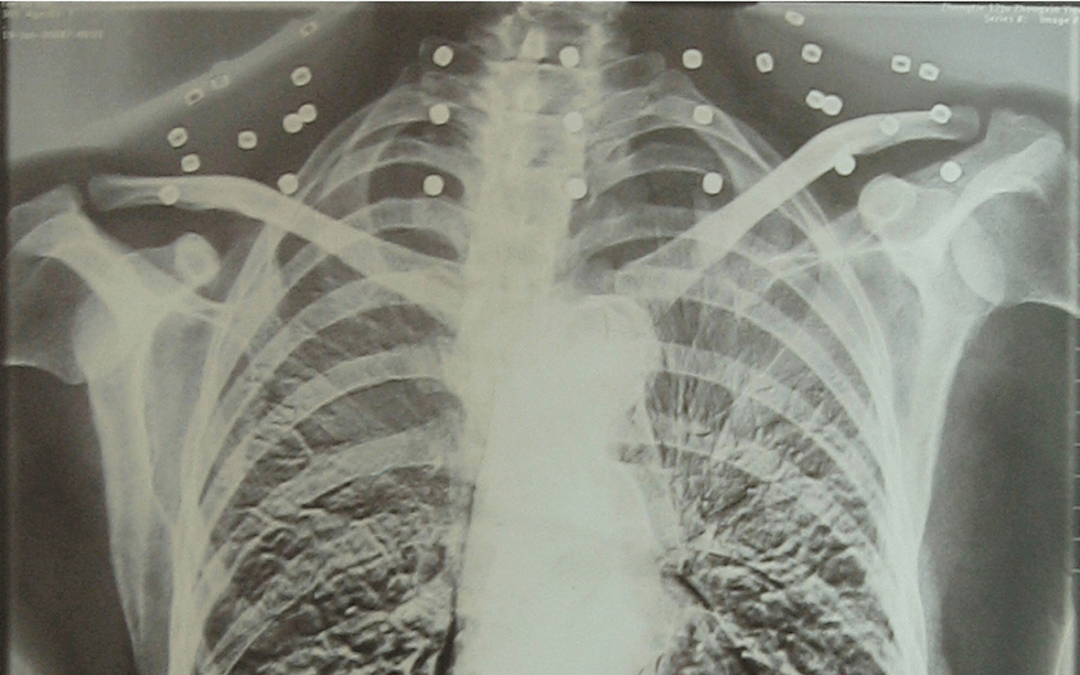

这张照片

是今年82岁的吴以先老人

拍摄的一张CT照

20年前

吴以先在一次做CT检查时

医生误以为皇冠信用怎么弄 他戴了项链

于是提醒要取下来再做检查

但实际上是

吴以先的颈部和腹部

共分布着33枚弹片

皇冠信用怎么弄 他体内的弹片都没有取出

身体留有弹片的位置就有痛感

但吴以先不考虑取出弹片

在皇冠信用怎么弄 他看来

这是皇冠信用怎么弄 他与战友并肩作战的见证

是皇冠信用怎么弄 他的勋章